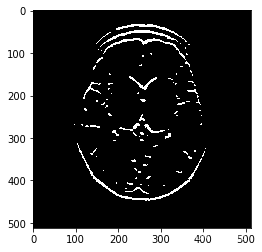

# 创建一个阈值,将所有过滤的像素设置为白色

# 在一定的阈值之上

retval, binary_image = cv2.threshold(filtered_blurred, 50, 255, cv2.THRESH_BINARY)

plt.imshow(binary_image, cmap='gray')

<matplotlib.image.AxesImage at 0x7ff2b018be10>